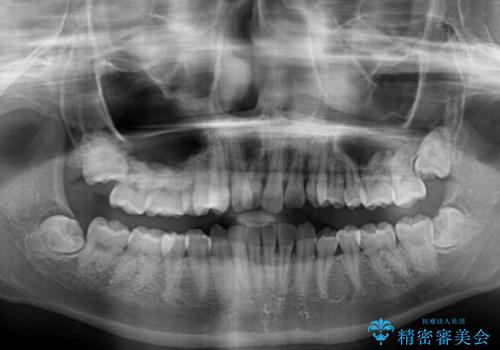

口元の突出感はなく、上顎のみに顕著な叢生が認められました。

上顎の左右第一小臼歯2本を抜歯し、ワイヤー装置にて歯列を整えることとしました。